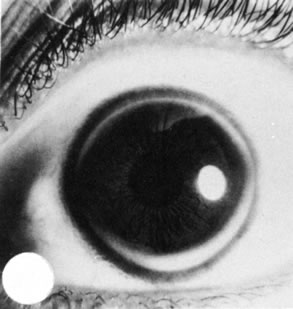

Megalocornea

Megalocornea exists when the largest corneal diameter is greater than 13 mm (Fig. 1).19,25 Megalocornea is a primary overgrowth rather than a secondary distention of the cornea.

Fig. 1. Megalocornea. A. The corneal diameter measures 15 mm. The remainder of the eye is normal. B. Megaloglobus consists of an enlarged cornea and globe. C. Megalocornea in the brother of the patient shown in A (a third brother also had megalocornea). The corneal diameter measures 16 mm. D. The crystalline lens is dislocated, and chronic open angle glaucoma is present. (Courtesy of SEI Photoarchives.)

The condition is not progressive. The cornea clinically is normal, although associated prominent iris processes and a heavily pigmented trabecular meshwork may occur. Myopia, high astigmatism, anterior embryotoxon, Krukenberg's spindles, a pigmentary-like glaucoma, and cataract also have been found in association with megalocornea. The lens may dislocate later in life and cause secondary glaucoma. Associated systemic conditions include osteogenesis imperfecta, Marfan syndrome, and Alport's syndrome. The inheritance pattern most commonly found is sex-linked recessive (Xq21.3-q22 region)26 although autosomal dominant and autosomal recessive cases have been identified.

Histologically, megalocornea shows a normal-sized cornea but an increased length and thickness from the end of Bowman's membrane to sclera (limbal region). Endothelial cell density by specular microscopy is normal. An increased endothelial cell population suggests a process of total corneal hyperplasia.27